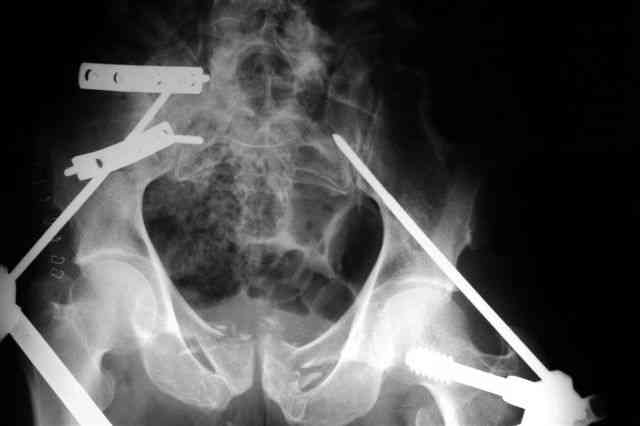

В приложении послеоперационные картинки.

При поступлении передняя рама (фиксация просто за гребни), соединенная с мыщелками бедра.

После стабилизации состояния перевернуть больного на живот или на бок, пару винтов закрыто через заднюю ость трансфрактурно в крыло слева (если не нравится стояние фрагмента, можно предворительно задним латеральным доступом отрепонировать), справа не очень понятно куда идет перелом крыла, но если фиксировать, то пластиной по наружной стороне.

Интраоперационно у меня не возникло сомнений , что Шанцы прошли через КП сочленения: сначала провёл Шанц справа при открытой ране после фиксации КП

сочленения пластинами и контролем ЭОПа инлет и аутлет проекциях, определившись с углом введения винта. затем слева - под Рг-контролем, отступив на 2 см латеральнее нижней ости, чтобы не провалиться в таз.